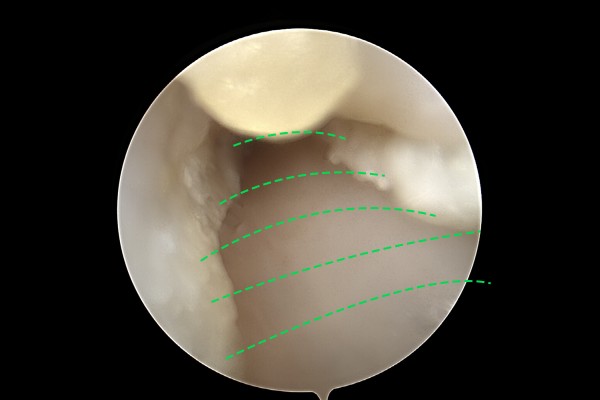

bf9d6fdaf4051a39be384f068acb231c_1757646390_5771.jpg

정중신경을 압박하는 횡수근인대를 절개하여 좌/우로 나눠줍니다.